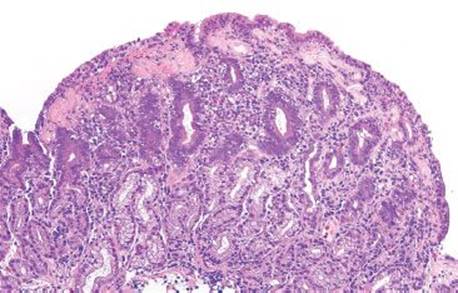

Figure 2.143 Collagenous gastritis pattern, olmesartan. At scanning magnification, this gastric biopsy has a prominent pink band below the surface epithelium. Focal areas of surface epithelium have also sheared off (far left), a characteristic finding in collagenous enteritis. Most cases are not as obvious as this example, and may require confirmation with a Masson’s trichrome stain to highlight the collagen deposition.

Collagenous gastritis is characterized by the deposition of a subepithelial collagen band and accompanying inflammatory infiltrate (Fig. 2.143).99,109–112 The pathogenesis of this rare disease remains unclear. The disease is more common in adults (range from 1 to 77 years), in whom associations include lymphocytic gastritis (33%), celiac disease or collagenous enteritis (25%), collagenous colitis, other immune-mediated disorders (such as Hashimoto thyroiditis, Sjögren syndrome, and polymyositis), Helicobacter, and medication injury (i.e., olmesartan). In contrast, associated intestinl and autoimmune diseases are not reported in children with collagenous gastritis. In the pediatric setting, endoscopic findings include a nodular, erythematous mucosa, and these findings are usually limited to the stomach. By comparison, endoscopic findings in adults typically include gastric atrophy with diffuse involvement of the gastrointestinal tract. Histologically, lamina propria lymphoplasmacytosis, patchy subepithelial collagen deposition of variable thickness, injury to and detachment of the surface epithelium, and glandular atrophy are seen (Figs. 2.143–2.151). Because the pathogenesis of collagenous gastritis is so poorly understood in children, treatment remains challenging and poorly defined. For adults, treatment of any underlying associated diseases is recommended, such as a gluten-free diet in patients with celiac disease, steroids in patients with collagenous colitis, and discontinuation of offending medications (i.e., olmesartan).